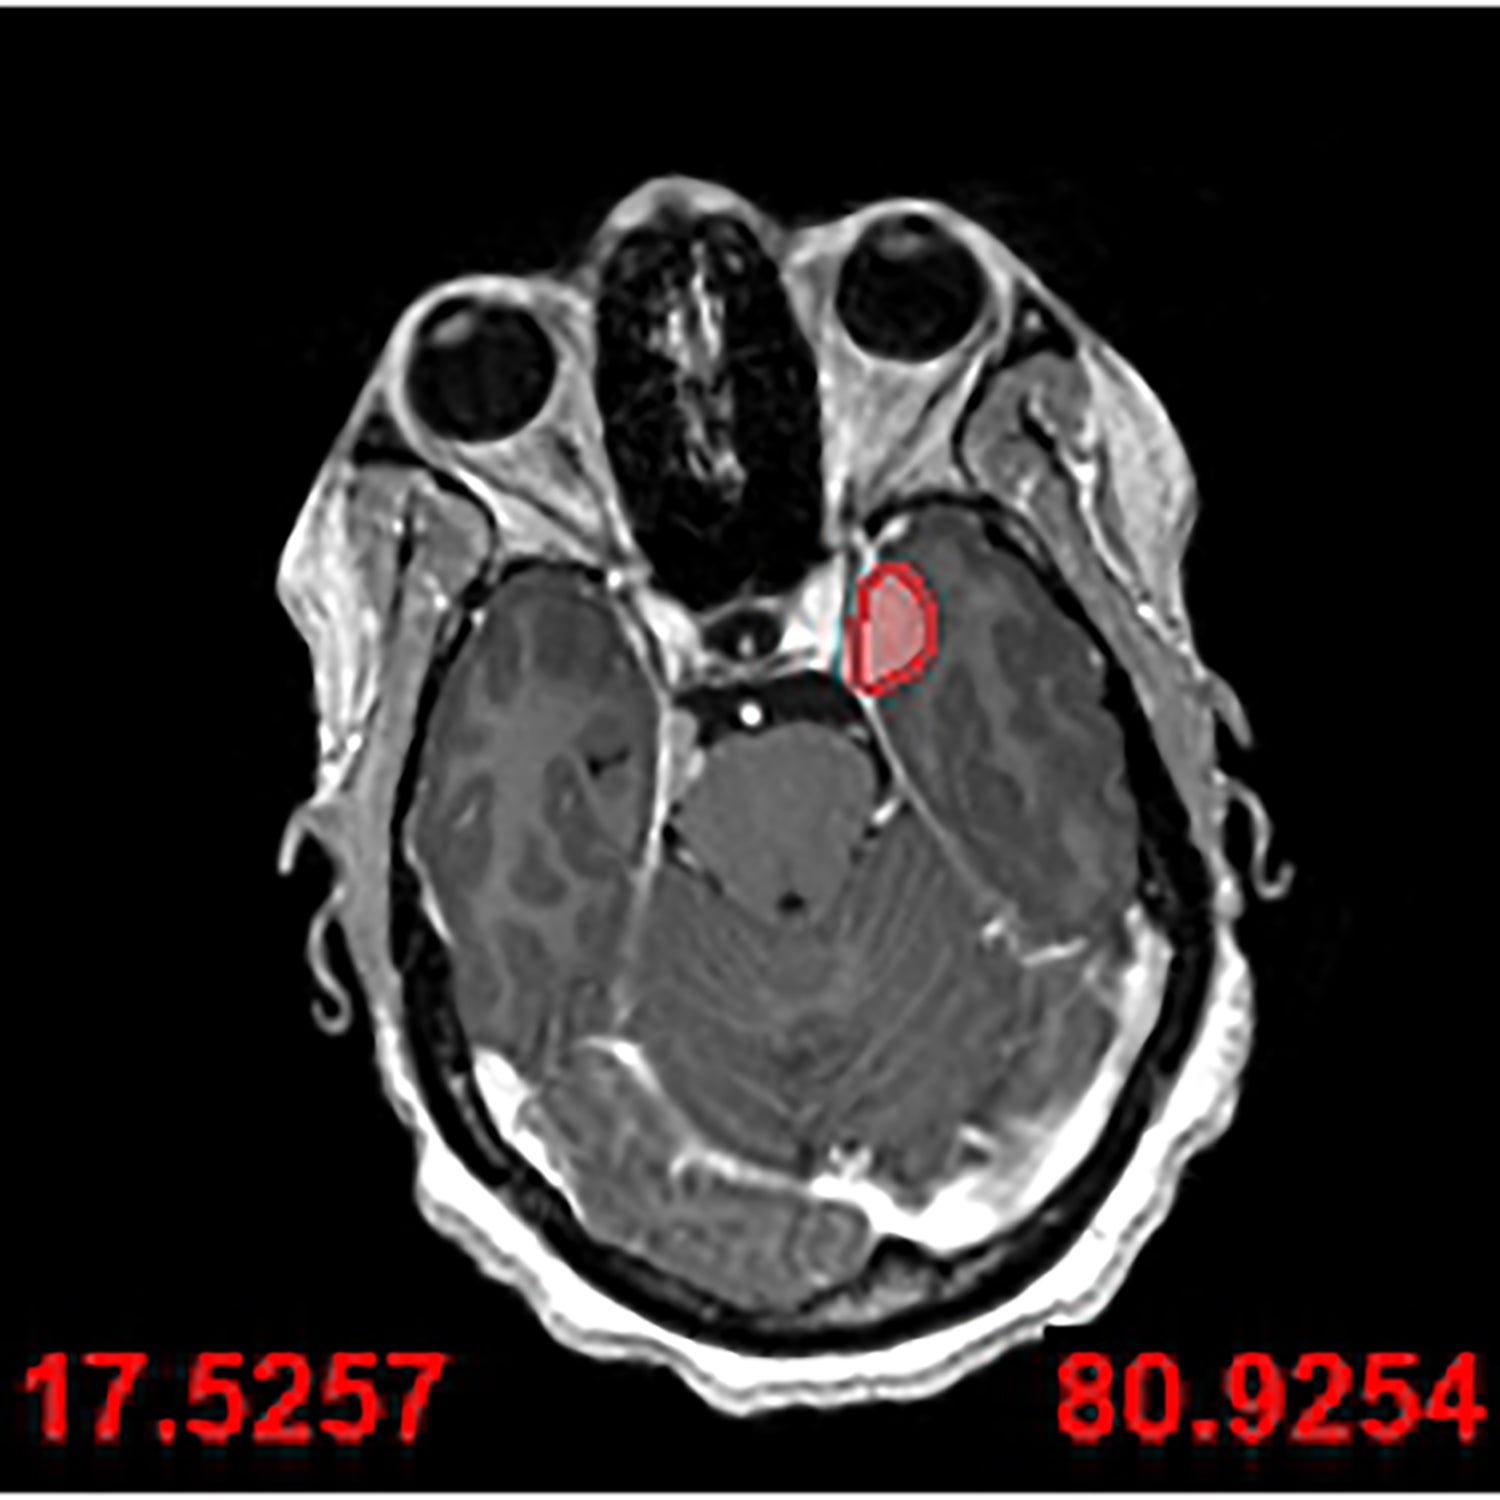

Mother-of-three Ruvimbo Kaviya had a meningioma removed from the space located beneath the brain and behind the eyes.

Many of these types of tumours would have previously been considered inoperable by doctors as they are situated in an area called the cavernous sinus.

She was eventually diagnosed with a meningioma in 2023 with a second one also found in October that year.